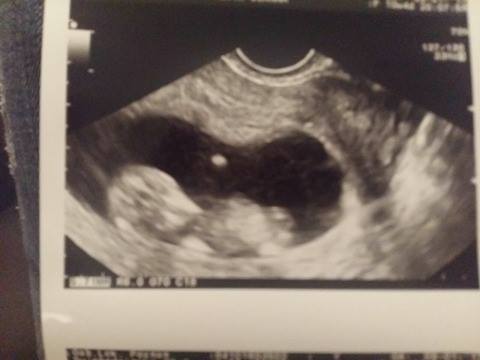

Cześć Kochane. Po powrocie do pracy mam dużo mniej czasu na regularne odwiedzanie forum i widzę, że mam sporo zaległości. Ja była dziś na USG i wszystko super. Maleństwo bardzo się ruszało więc ciężko było zrobić zdjęcie, ale doktor była bardzo zadowolona i mówiła, że wszystko ok.

Hihi, na pierwszym zdjęciu wygląda jak kosmita [emoji89] [emoji106]Cześć Kochane. Po powrocie do pracy mam dużo mniej czasu na regularne odwiedzanie forum i widzę, że mam sporo zaległości. Ja była dziś na USG i wszystko super. Maleństwo bardzo się ruszało więc ciężko było zrobić zdjęcie, ale doktor była bardzo zadowolona i mówiła, że wszystko ok.

Zobacz załącznik 790873 Zobacz załącznik 790872 Zobacz załącznik 790871